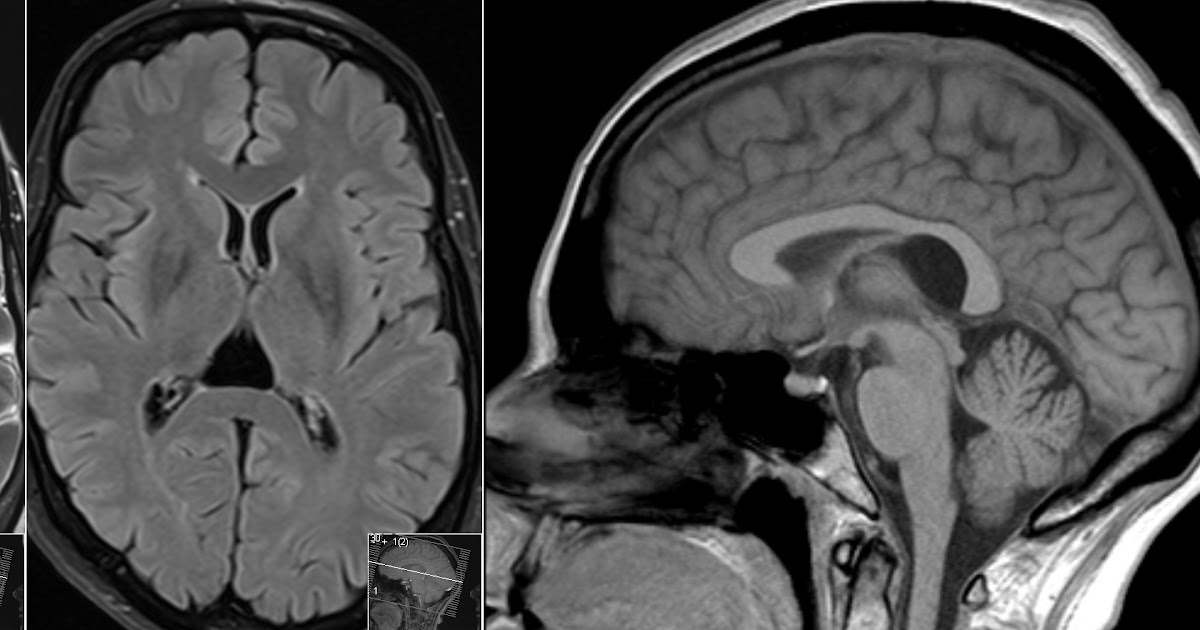

From radiopaedia.org

Cavum velum interpositum Image Cavum Velum Interpositum Effects cavum velum interpositi is the space between the layers of the tela choroidea of the third ventricle. abstract cavum velum interpositi is the space between the layers of the tela choroidea of the third ventricle. the term cyst of the velum interpositum or cavum veli interpositi cyst should be used when the lesion is of round. . Cavum Velum Interpositum Effects.

Cavum velum interpositum cyst Image Cavum Velum Interpositum Effects abstract cavum velum interpositi is the space between the layers of the tela choroidea of the third ventricle. Identify the etiology of cavum veli interpositi and the medical conditions. cavum veli interpositi is a rare anatomical variation characterized by an enlarged space within the velum. cavum velum interpositi is the space between the layers of the tela. Cavum Velum Interpositum Effects.